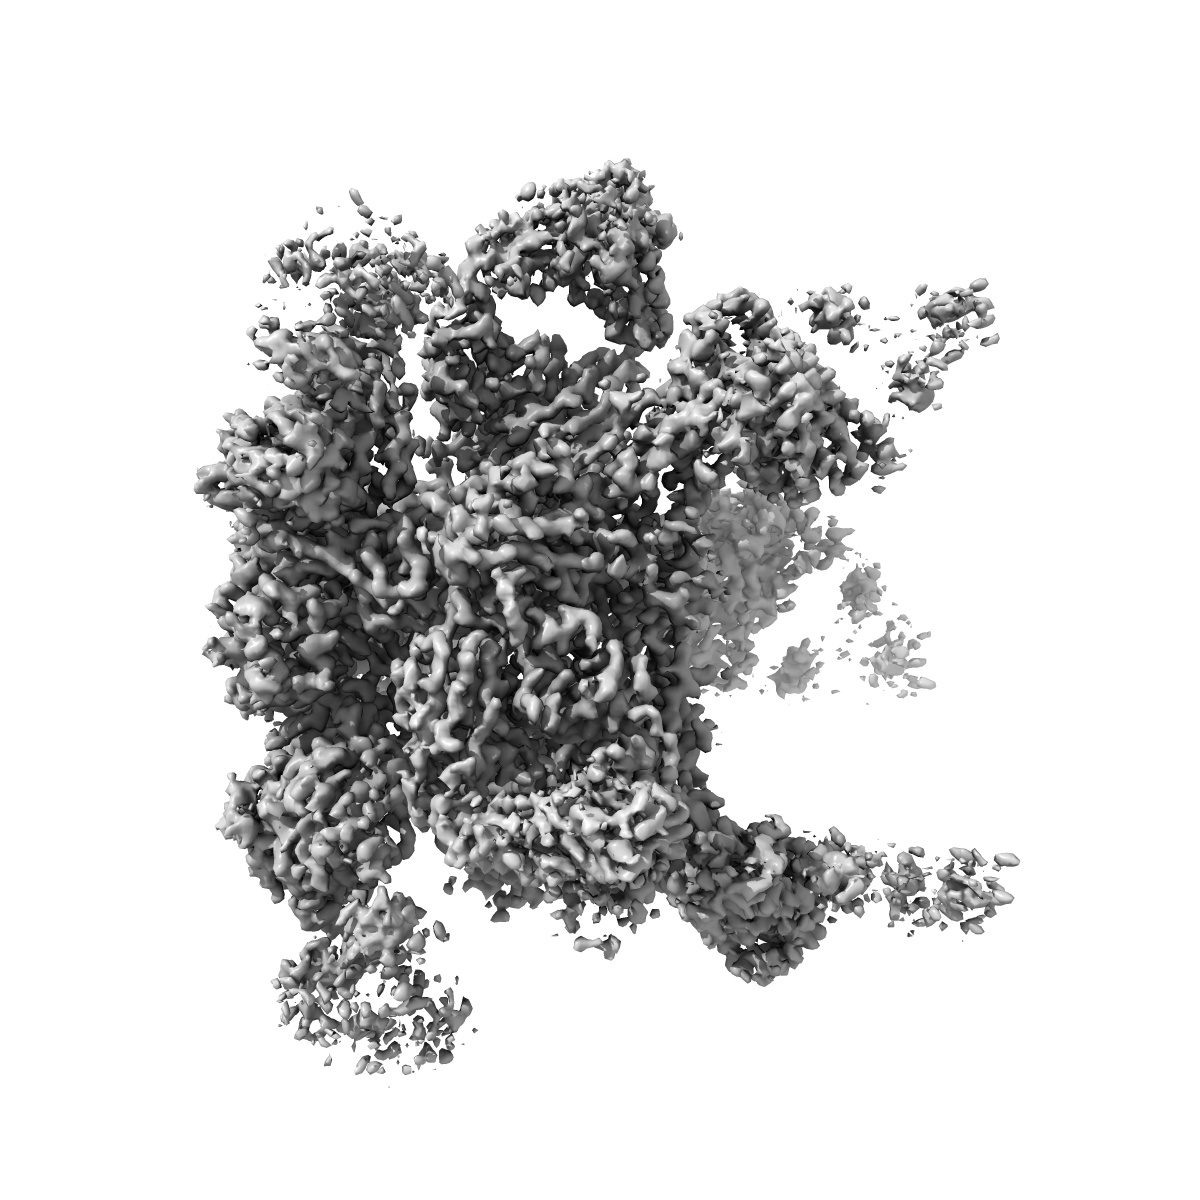

Cryo-EM structure at 3.2 A resolution of HIV-1 fusion peptide-directed antibody, A12V163-b.01, elicited by vaccination of Rhesus macaques, in complex with stabilized HIV-1 Env BG505 DS-SOSIP, which was also bound to antibodies VRC03 and PGT122

Single-particle3.18 Å

Sample: Quaternary complex of HIV-1 Env BG505 DS-SOSIP with antibodies A12V163-b.01, VRC03 and PGT122.